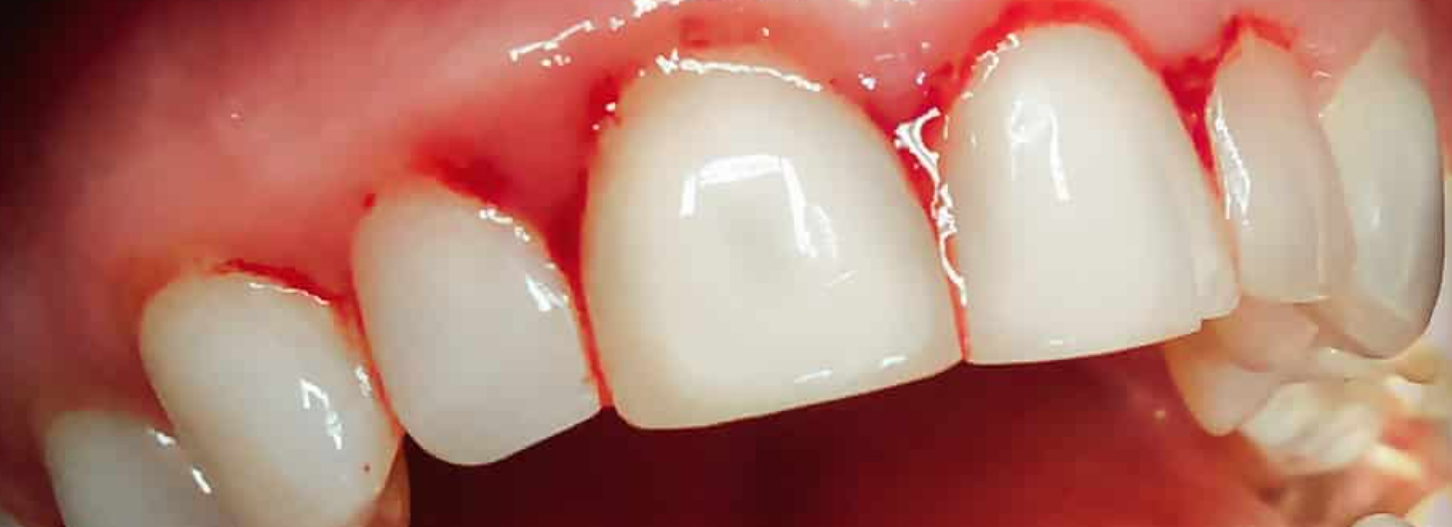

La gingivite chronique : la gingivite est la maladie parodontale la plus courante et la moins grave . Il s’agit d’une inflammation localisée ou généralisée de la gencive qui agit sur le parodonte, un ensemble de tissus qui entoure les dents. Les personnes les plus susceptibles de contracter ce type de maladies sont les femmes enceintes ou qui prennent la pilule contraceptive, les personnes atteintes de diabète ou encore celles qui consomment certains types de médicaments.

- des saignements lors du brossage ou lors des repas,

- des inflammations, rougeurs et gonflements des gencives,

La gingivite

La gingivite est une infection dentaire très courante. Certains signes avant-coureurs doivent vous alerter : un gonflement, une rougeur ou un saignement au niveau de la gencive. Il faut alors consulter rapidement votre dentiste pour éviter que la gingivite n’entraîne des problèmes parodontaux.